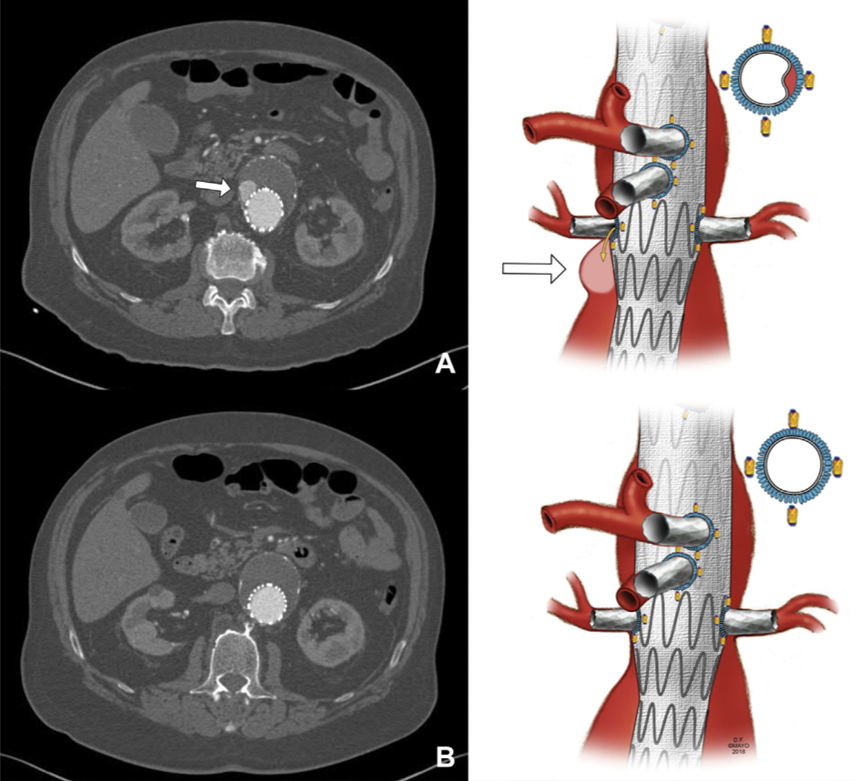

患者女,68岁,3年前因腹主动脉瘤于我院行EVAR+肠系膜上动脉、双肾动脉支架植入,术后半年因内漏行瘤腔弹簧圈填塞。2022年初再次触及腹部搏动性包块,入院后检查提示肠系膜上动脉支架脱出,导致IlIc型内漏 (a,b)。在原支架内置入一覆膜支架后消除内漏(c)。

分支支架滑脱的原因可能在于:

1. 选用的fluency支架可能较为僵硬。

2. 预制窗口过小,明显小于分支支架直径而将分支支架挤出主体支架。

3. 分支支架直径小于分支血管直径,导致分支支架活动度增加。

4. 分支支架进入主体支架过短。